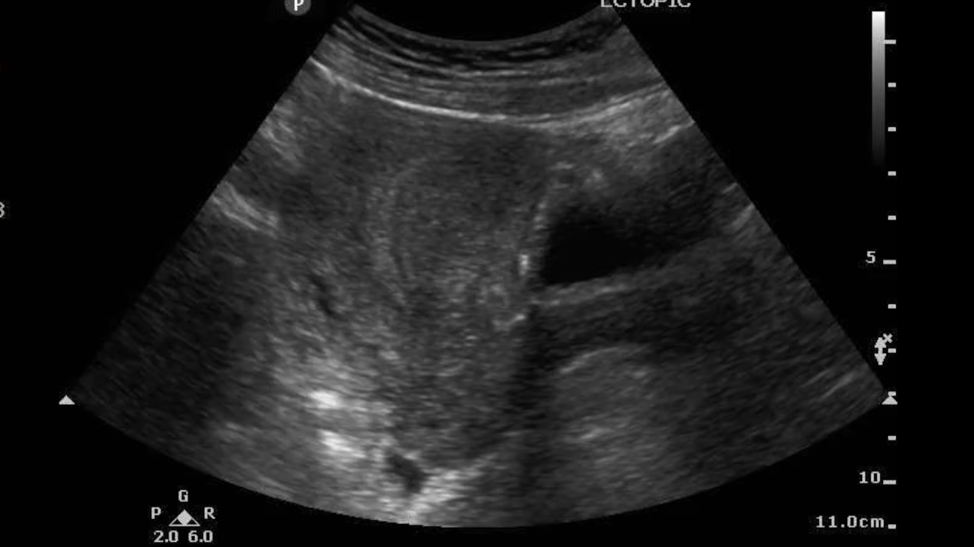

A transabdominal ultrasound is performed.

Figure 4. No intrauterine pregnancy visualized.